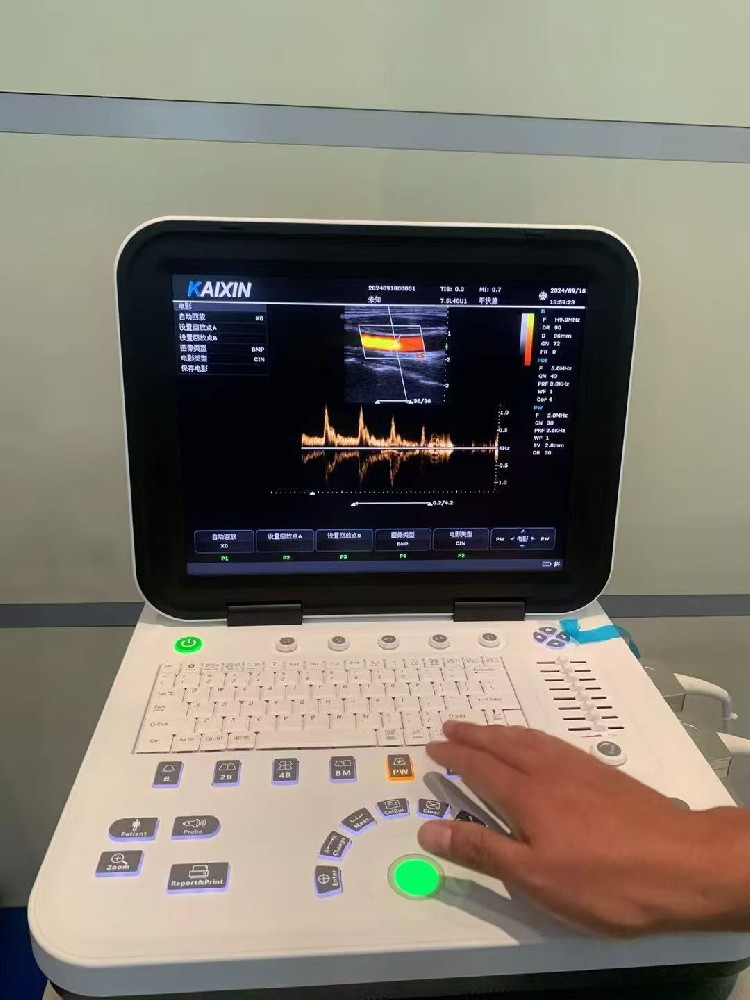

便携B超与碎石机配合,核心应用是在泌尿系统结石治疗中实现“实时定位-精准碎石-疗效确认”的闭环操作,尤其适用于门诊、急诊或床旁等移动医疗场景。1. 核心应用场景:泌尿系统···...

具体重要性体现在以下三点: 1、适配基层场景:体积小、重量轻,可在村委会、村卫生室等简易场所快速部署,无需专门的大型检查室,甚至能为行动不便的老人上门检查,极大提升了下乡···...